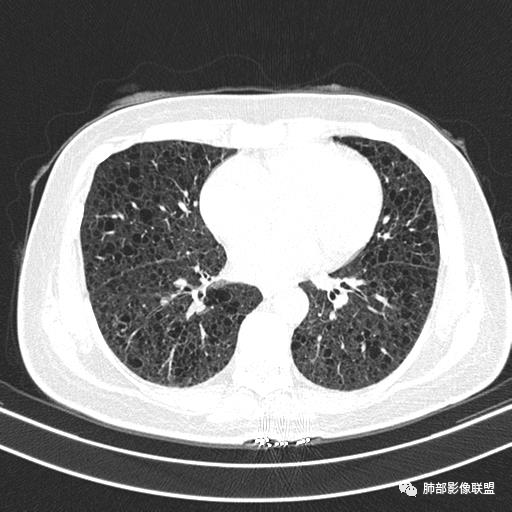

双肺弥漫囊腔,累及肋膈角,囊腔形态相对规则单一。

CT平扫示双肺弥漫分布大小不等囊状薄壁透光区,无内、中、外带分布差异,间质稍示增厚。拟LAM

中年女性育龄期妇女,咳嗽气喘,无吸烟史,有苯吸入史。影像:双肺弥漫均匀小囊腔,无明显分布优势,囊腔形态欠规则,壁薄,部分囊腔边缘血管征,伴双肺弥漫磨玻璃影,无结节,考虑lam,鉴别苯中毒肺损伤,囊腔多有分布优势,小叶中心分布为主,形态规整等

双肺多发大小相近的囊状影,分布趋势趋于一致,中年女性,考虑LAM。部分囊内见血管及分隔影,小叶中心性肺气肿代排

CT表现:双肺弥漫大小不等的薄壁囊腔,囊壁<2mm,外形规则,血管影多位于囊腔周围,囊腔之间肺组织正常,随着疾病进展到晚期,囊腔变大、增多,不可胜数,囊腔可融合成较大的囊,与肺气肿相似,形成间质性肺纤维化。部分病例可出现结节影。